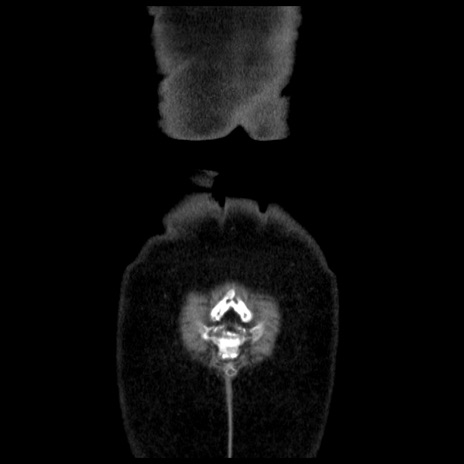

横断像